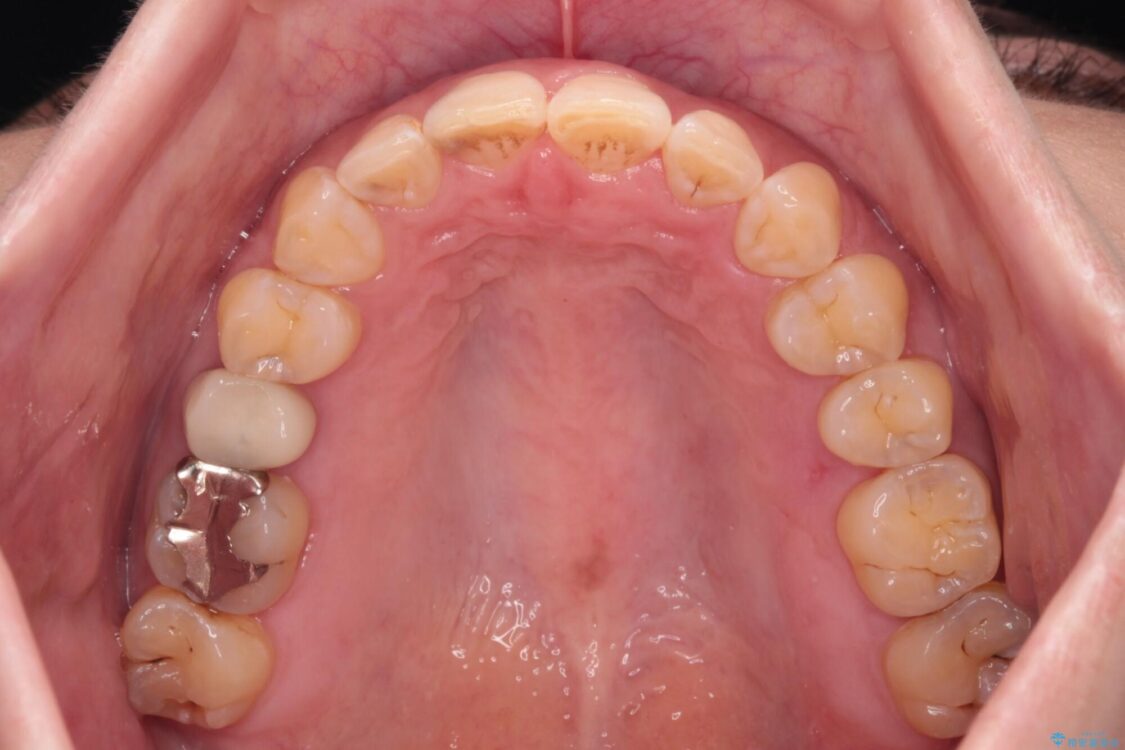

飛び出た上の前歯を気にして来院された患者様です。

奥歯の咬み合わせは、上顎歯列が理想的な一よりも数mm前方にある状態でした。

治療前

• 【モニター】飛び出た前歯を整えたい ワイヤー矯正治療 治療前画像